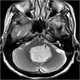

Tumor at fourth ventricle

An ependymoma is a tumor that arises from the ependyma, a tissue of the central nervous system. Usually, in pediatric cases the location is intracranial, while in adults it is spinal. [Source: Wikipedia ]